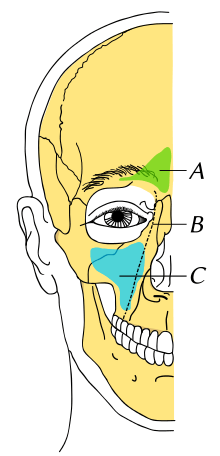

Maxillary implant

A maxillary implant is an implant that is placed between jaw and the maxillary sinuses. It is inserted during a sinus lift or augmentation and used to increase the amount of bone to support dental implants.[1] Implants are either inserted after drilling or by using a non-drilling method known as the osteotome technique.[1] Issues such as bulging within the sinuses can occur with maxillary implants.[2][3]